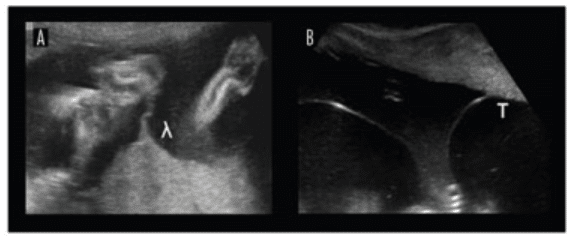

Nesse sentido, a presença do sinal do “lambda” sugere gestação dicoriônica, ao passo que o sinal do “T” é mais característico das gestações monocoriônicas. Portanto, observar atentamente a inserção da membrana na placa corial é um passo indispensável durante a ultrassonografia precoce.

Na imagem abaixo é possível visualizar o sinal do lambda [A] e o sinal do T [B], característicos das gestações gemelares di e monocoriônicas, respectivamente: